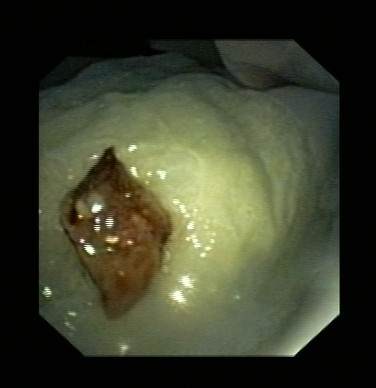

近日,呂先生有門診收入我呼吸科住院治療,全體醫(yī)護(hù)人員高度重視,認(rèn)真討論病情。我科吳主任仔細(xì)看過呂先生的CT片后,觀察到右下肺氣管內(nèi)異物,于是決定行支氣管鏡檢查。在氣管鏡室,吳主任給他做了支氣管鏡檢查,發(fā)現(xiàn)呂先生右下肺支氣管內(nèi)卡著一個黑黑的異物,由于時間太久,異物周圍已充血水腫,表面有膿苔及壞死物覆蓋,清除膿苔及壞死物后,可見異物被肉芽組織緊緊包埋。吳主任成功取出了呂先生氣管內(nèi)異物,并吸出了氣管內(nèi)膿性分泌物。呂先生咳嗽癥狀立刻改善,行氣管鏡檢查后第二天患者無咳嗽癥狀,順利出院。

圖表2壞死物吸出后可見異物